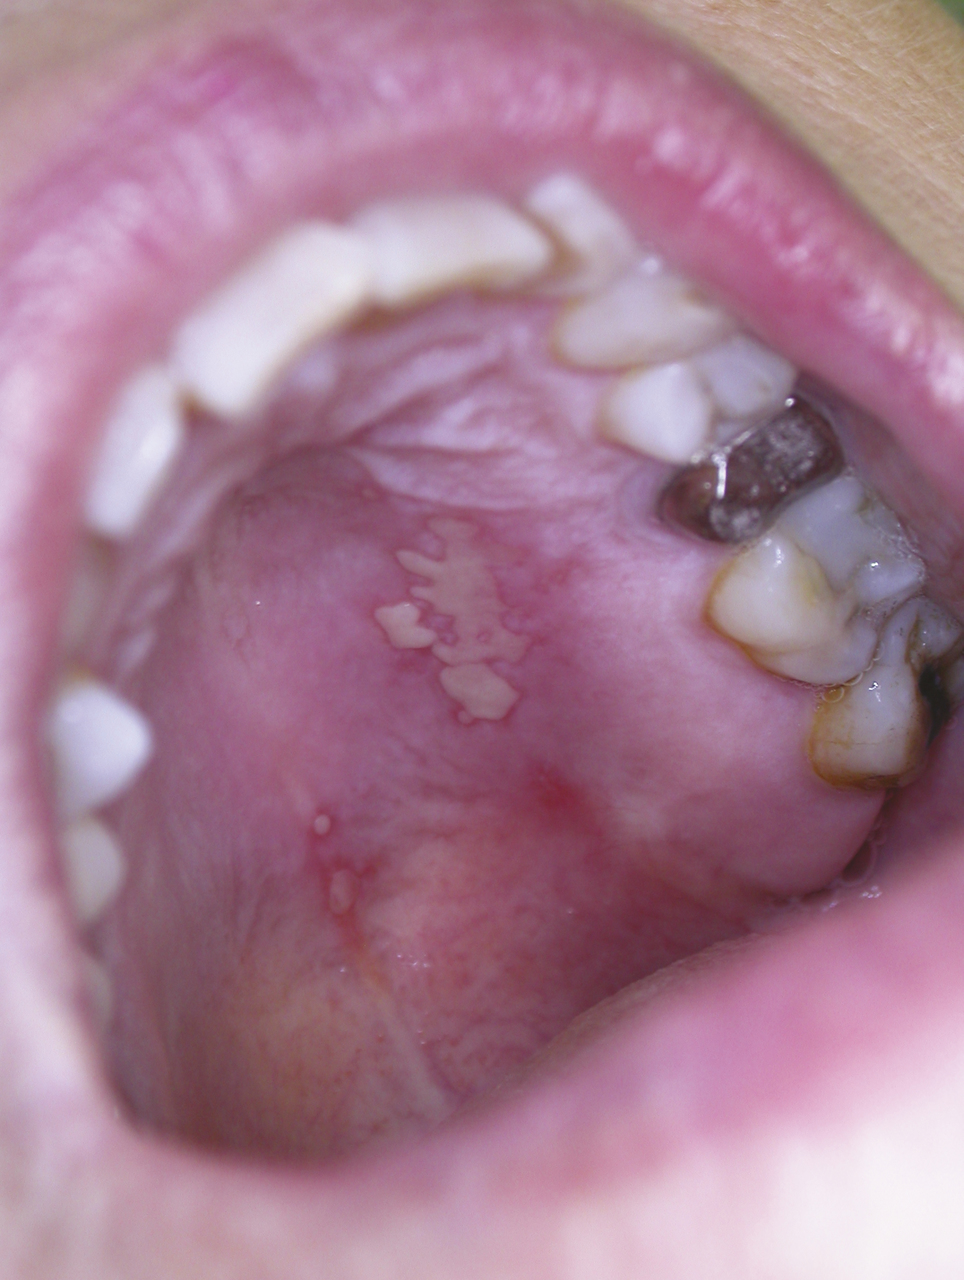

Si les aphtes banals et les traumatismes représentent les causes les plus fréquentes d’ulcérations buccales,1 leur diagnostic repose sur certaines caractéristiques cliniques et ne doit pas faire méconnaître les autres causes dominées en sévérité par le carcinome épidermoïde. L’aphte buccal est fréquent, souvent banal, ses critères diagnostiques sont précis et ce diagnostic est souvent porté par excès. C’est une ulcération le plus souvent ronde, très douloureuse, de quelques millimètres de diamètre à bords réguliers, entourée d’un halo rouge inflammatoire, son fond est jaune « beurre frais » (fig. 1 ), et il repose sur une base souple. Les aphtes siègent préférentiellement sur les muqueuses souples (lèvres, joues, langue), l’atteinte gingivale ou palatine est rare. Il guérit spontanément en une dizaine de jours. Une ulcération ne correspondant pas à cette description doit faire rediscuter le diagnostic d’aphte dans la crainte de méconnaître un diagnostic plus sévère comme un carcinome épidermoïde débutant (fig. 2 ). Un aphte « géant » est défini par un diamètre supérieur à 1 cm (fig. 3 ) ; c’est une forme sévère extrêmement douloureuse pouvant demander plusieurs semaines voire plusieurs mois pour cicatriser en l’absence de traitement. Cette forme est peu fréquente et peut être liée à une immunodépression.

Les papillomavirus humains qui ont un tropisme pour les kératinocytes des épithéliums malpighiens sont responsables de tumeurs bénignes (verrues, papillomes, condylomes) ; certains d’entre eux sont oncogènes (col de l’utérus, carcinomes épidermoïdes pharyngolaryngés) ; leur implication dans la survenue de carcinomes épidermoïdes de la cavité buccale n’est pas démontrée. Les papillomes sont des élevures de quelques millimètres de diamètre, indolores à surface kératosique (fig. 7 ), des verrues digitales sont parfois à l’origine de l’auto-inoculation. Les condylomes acuminés sont rares sur la muqueuse buccale, leur transmission est sexuelle. L’évolution spontanée est variable, ils persistent ou se multiplient mais peuvent également régresser spontanément. La présence de papillomes multiples (fig. 8 ) fait rechercher une immunodépression. Le traitement repose sur la destruction des lésions (chirurgie, laser CO2) ; les récidives sont possibles.